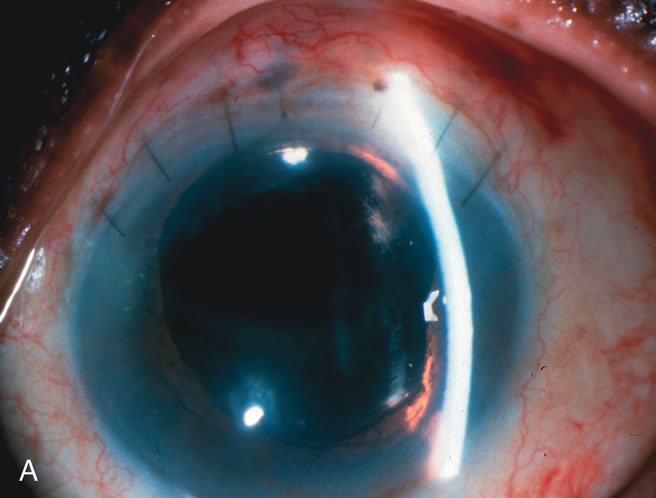

Fig. 1. The anatomic advantage of small incision cataract surgery for the glaucoma patient. A. Long-term bleb function with a large cataract incision is difficult to achieve with either ECCE-trabeculectomy or trabeculectomy followed later by ECCE. This bleb failed to form sufficiently when combined with large incision ECCE. The inflammation, bleeding, and long-term wound healing with stimulation of fibroblasts associated with this technique are more likely to cause bleb failure. In addition, the increased iris manipulation necessary to deliver the nucleus and subsequent iris repair adds to the long-term breakdown of the blood aqueous barrier. B and C. Two-site phacotrabeculectomy has the advantage of small incision cataract surgery combined with separate site trabeculectomy. The incision size is one third the size of the standard ECCE. The inflammation is less severe, and cataract wound healing is confined to the temporal area. Visual rehabilitation with phacoemulsification and foldable IOL is much faster. Phacoemulsification allows successful lens extraction even in the unfriendly environment of a smaller pupil compared with ECCE. The trabeculectomy is performed in an entirely different site, well away from the wound healing associated with temporal phacoemulsification. The likelihood of this filter functioning long-term is greater than with ECCE-trabeculectomy. D. The surgeon also has the option of single-site phacotrabeculectomy with foldable IOL. Both the lens extraction and trabeculectomy are performed through one small 3.5-mm limbal incision.